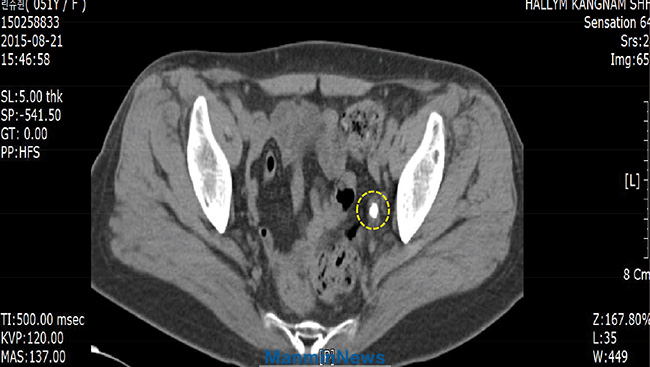

2015³â 8¿ù, Ç㸮 ºÎÀ§¿¡ ½ÉÇÑ ÅëÁõÀÌ ´À²¸Á³°í µî µÚÂʵµ ¾ÆÆÍ½À´Ï´Ù. ÀáÀÚ¸®¿¡ ´©¿öµµ ÅëÁõ ¶§¹®¿¡ ÇÑ ½Ã°£ÀÌ Ã¤ ¸ø µÅ¼ ÀϾ¾ß¸¸ ÇßÁö¿ä. ¼Òº¯À» º¼ ¶§´Â °íÅëÀÌ ³Ê¹« ½ÉÇß°í Àß ³ª¿ÀÁöµµ ¾Ê¾Ò½À´Ï´Ù.

º´¿ø °Ë»ç °á°ú, ¿ä·Î°á¼®À̾ú½À´Ï´Ù. ÀÇ»ç´Â °á¼®ÀÇ Å©±â°¡ ³Ê¹« Ä¿¼ ·¹ÀÌÀú·Î Á¦°ÅÇÒ ¼ö ¾ø´Ù¸ç ÀÔ¿øÇÏ¿© ¼ö¼úÀ» ¹ÞÀ¸¶ó°í ¸»Çß½À´Ï´Ù. ±×·¯³ª Àú´Â Çϳª´Ô ¹æ¹ýÀ¸·Î ¿ä·Î°á¼®À» Ä¡·á¹Þ¾Æ¾ß°Ú´Ù°í ¸¶À½¸Ô¾úÁö¿ä.

2015³â 10¿ù ÃÊ, ¸¶Ä§ ±³È¸ ⸳ 33ÁÖ³âÀ» ¸Â¾Æ »ê»ó±âµµ Áß¿¡ ³»·Á¿À½Å ´çȸÀå ÀÌÀç·Ï ¸ñ»ç´Ô²² ¹ÏÀ½À¸·Î ±âµµ¸¦ ¹Þ¾Ò½À´Ï´Ù. ÀÌÈÄ ¸ÅÀÏ ´çȸÀå´Ô ¼³±³¸¦ µè´ø Áß ¸¶À½¿¡ ÇÒ·ÊÇÏÁö ¸øÇϰí Ç÷±â¸¦ ³»¸ç ÁÖº¯ »ç¶÷µé¿¡°Ô ³ª¸¦ ÁÖÀåÇϰí, ¸»¾¸À» ¾Ë¸é¼µµ ÇàÇÔÀÌ ³Ê¹« ºÎÁ·Çß´Ù´Â »ç½ÇÀ» ±ú´Ý°í ¸¹Àº ȸ°³¸¦ ÇÏ¿´Áö¿ä. ±×·¯´ø Áß, ÅëÁõÀÌ »ç¶óÁ® 10¿ù 23ÀÏ º´¿ø¿¡ °¡¼ °Ë»çÇØ º¸´Ï °á¼®ÀÌ º¸ÀÌÁö ¾Ê´Â °ÍÀÔ´Ï´Ù. ÇÒ·¼·ç¾ß!

¼ö¼ú ¾øÀÌ´Â Á¦°Å°¡ ¾î·Æ´Ù´ø 1.3 cm³ª µÇ´Â ¿ä·Î°á¼®ÀÌ ¾Æ¹«·± ÀÇÇÐÀû Ä¡·á ¾øÀÌ ¿ÀÁ÷ Çϳª´Ô ±Ç´ÉÀ¸·Î Ä¡·áµÈ °ÍÀÔ´Ï´Ù. ÀÌ·¯ÇÑ ³î¶ó¿î ¿ª»ç¸¦ º£Ç®¾î ÁֽŠ»ì¾Æ °è½Å Çϳª´Ô²² ¸ðµç °¨»ç¿Í ¿µ±¤À» µ¹¸³´Ï´Ù.

±âµµ¹Þ±â Àü_ÁÂÃø ¿ä°ü¿¡ 1.3 cm Å©±âÀÇ °á¼®ÀÌ º¸À̰í ÀÖ´Ù.

±âµµ¹ÞÀº ÈÄ_ÁÂÃø¿¡ º¸¿´´ø 1.3 cm Å©±âÀÇ °á¼®ÀÌ »ç¶óÁ® º¸ÀÌÁö ¾Ê°í ÀÖ´Ù.